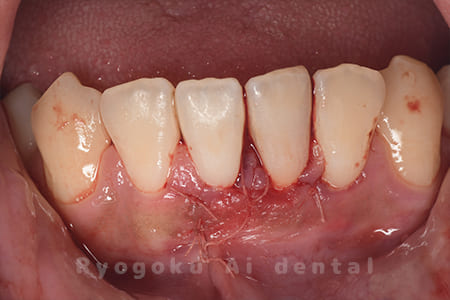

下の前歯の違和感が取れない、響く感じも強いとのことでご来院された患者様です。歯根端切除術を行い、術後の経過も良好です。

<リスク・副作用>

外科手術のため、術後に出血、痛みや腫れ、違和感を伴います。口腔内の状態によっては適応できないことがあります。歯根端切除で治らなければ抜歯を検討しなくていけない場合もあります。